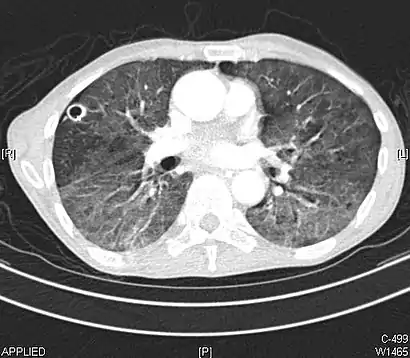

CT showing diffuse ground-glass opacities in periphery of both lungs in patient with COVID-19.

COVID-19

Ground-glass opacity is among the most common imaging findings in patients with confirmed COVID-19.[16][17] One systematic review found that among patients with COVID-19 and abnormal lung findings on CT, greater than 80% had GGOs, with greater than 50% having mixed GGOs and consolidation.[16] GGOs with mixed consolidation has most often been found in elderly populations.[18] Several studies have described a pattern among initial, intermediate, and hospital discharge imaging findings in the disease course of COVID-19. Most commonly, initial CT imaging reveals bilateral GGOs at the periphery of the lungs. During initial stages, this is most often found in the lower lobes, although involvement of the upper lobes and right middle lobe has also been reported early in the disease course.[16][18] This is in contrast to the two similar coronaviruses, SARS and MERS, which more commonly involve only one lung on initial imaging.[19][20] As the COVID-19 infection progresses, GGOs typically become more diffuse and often progress to consolidation.[11][18] This is sometimes accompanied by the development of a crazy paving pattern and interlobular septal thickening.[18] In many cases the most severe pulmonary CT abnormalities occurred within 2 weeks after symptoms began.[17] At this point, many individuals begin showing resolution of consolidation and GGOs as symptoms improve. However, some patients have worsening symptoms and imaging findings, with further increase in septal thickening, GGOs, and consolidation. These patients may develop lung "white-out" with progression to acute respiratory distress syndrome (ARDS) requiring treatment escalation.[17][21]

Preliminary reports have shown many patients have residual GGOs at time of discharge from the hospital. Due to the novelty of COVID-19, large studies investigating the long-term pulmonary CT changes have yet to be completed. However, long-term pulmonary changes have been seen in patients after recovery from SARS and MERS, suggesting the possibility of similar long-term complications in patients who have recovered from acute COVID-19 infection.[22]